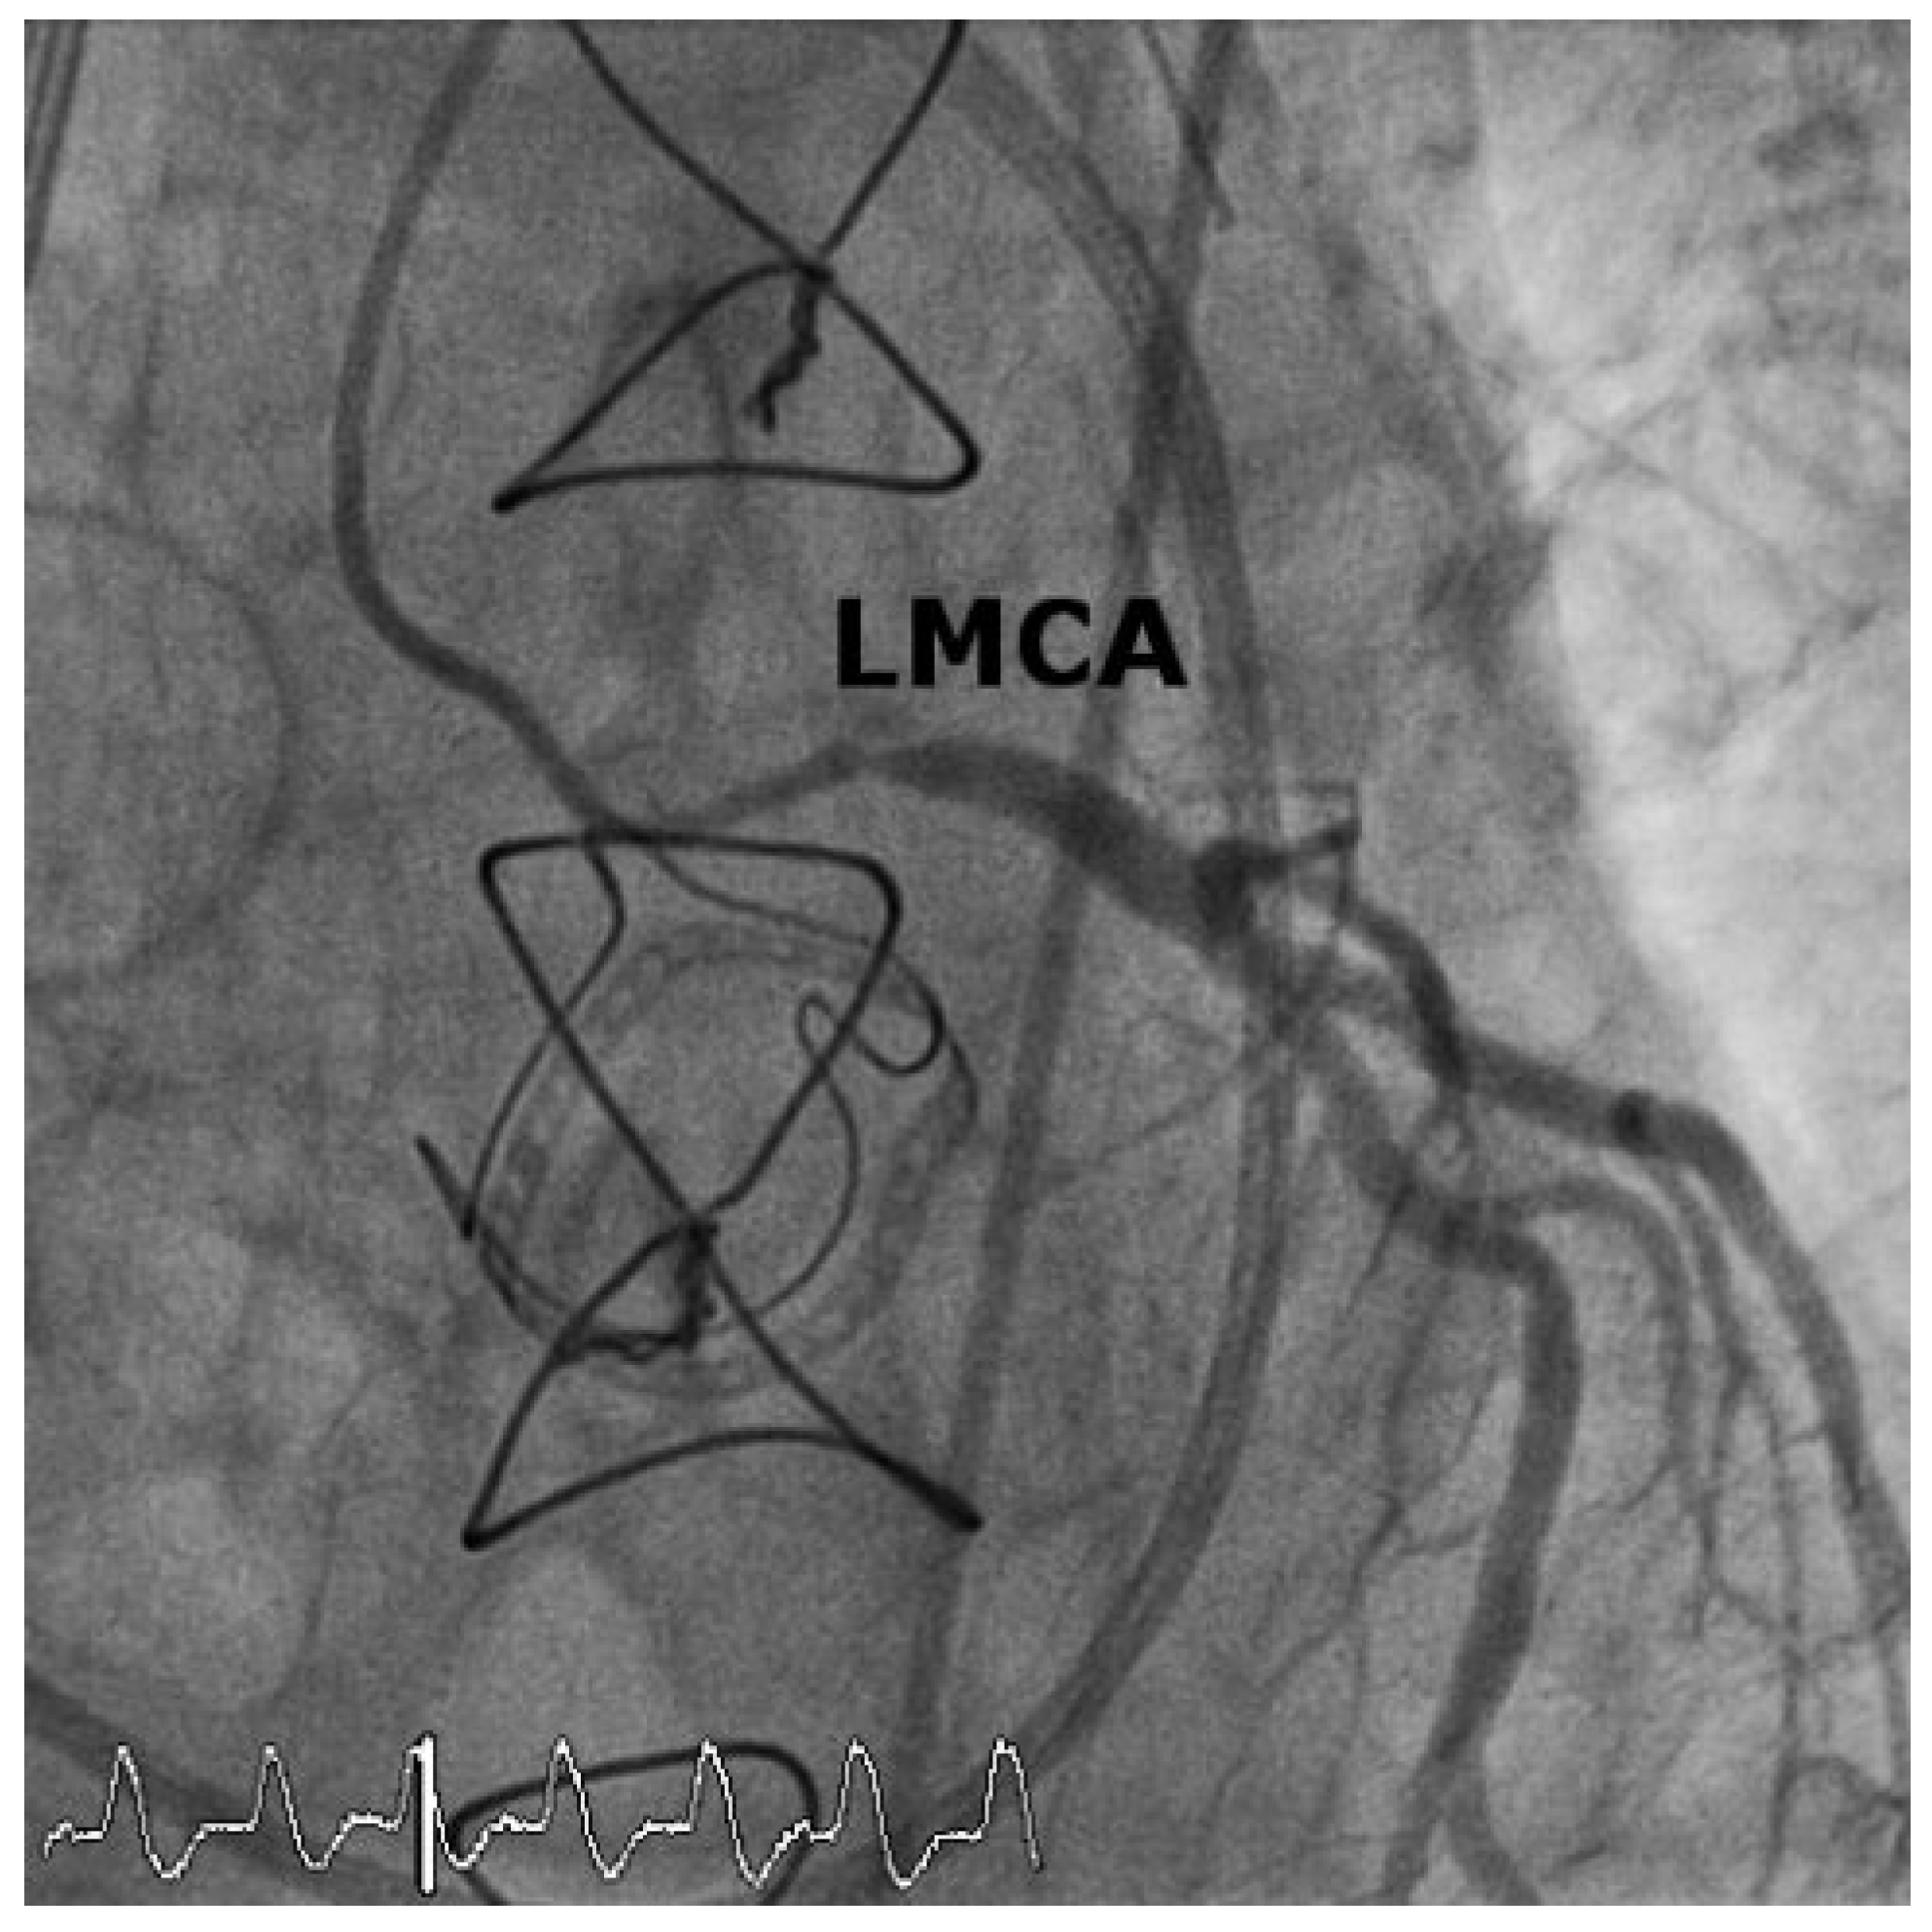

Case 1